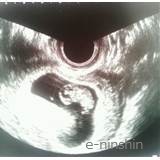

経膣エコーでは力を入れないように心がけました。内診台に座る緊張感も前回よりは落ち着きましたが、やはり慣れない内診には違和感を感じてしまったそうです。

エコー写真は左上が頭で、画像下部分が足にあたると説明をうけました。

頭や足の形ははっきりとわかれていないのですが、頭部分が大きめに写っています。たった2週間しかたっていないのに赤ちゃんが成長していることに、妊娠を強く実感しました。